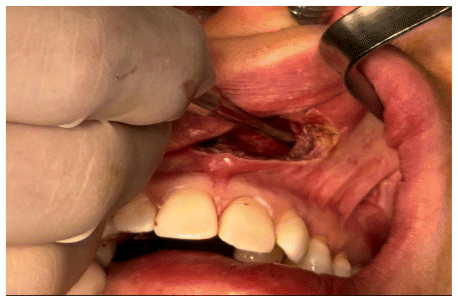

The surgical procedure was performed following minimally invasive orthognathic surgery, involving a mucoperiosteal incision in the anterior vestibular region of the maxilla. The surgical access measured approximately 2 cm, extending from one central incisor to the other. (Figure 4)

A subperiosteal dissection was performed in the nasomaxillary region, followed by the creation of a myomucosal tunnel in the posterior area of the maxilla to facilitate the passage of the implant. (Figure 5)